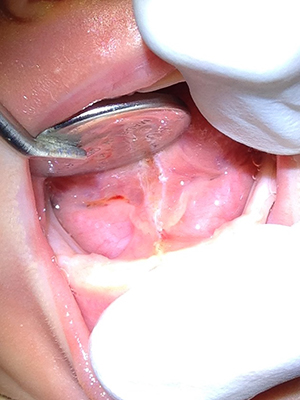

Frenulectomy before photo

Before